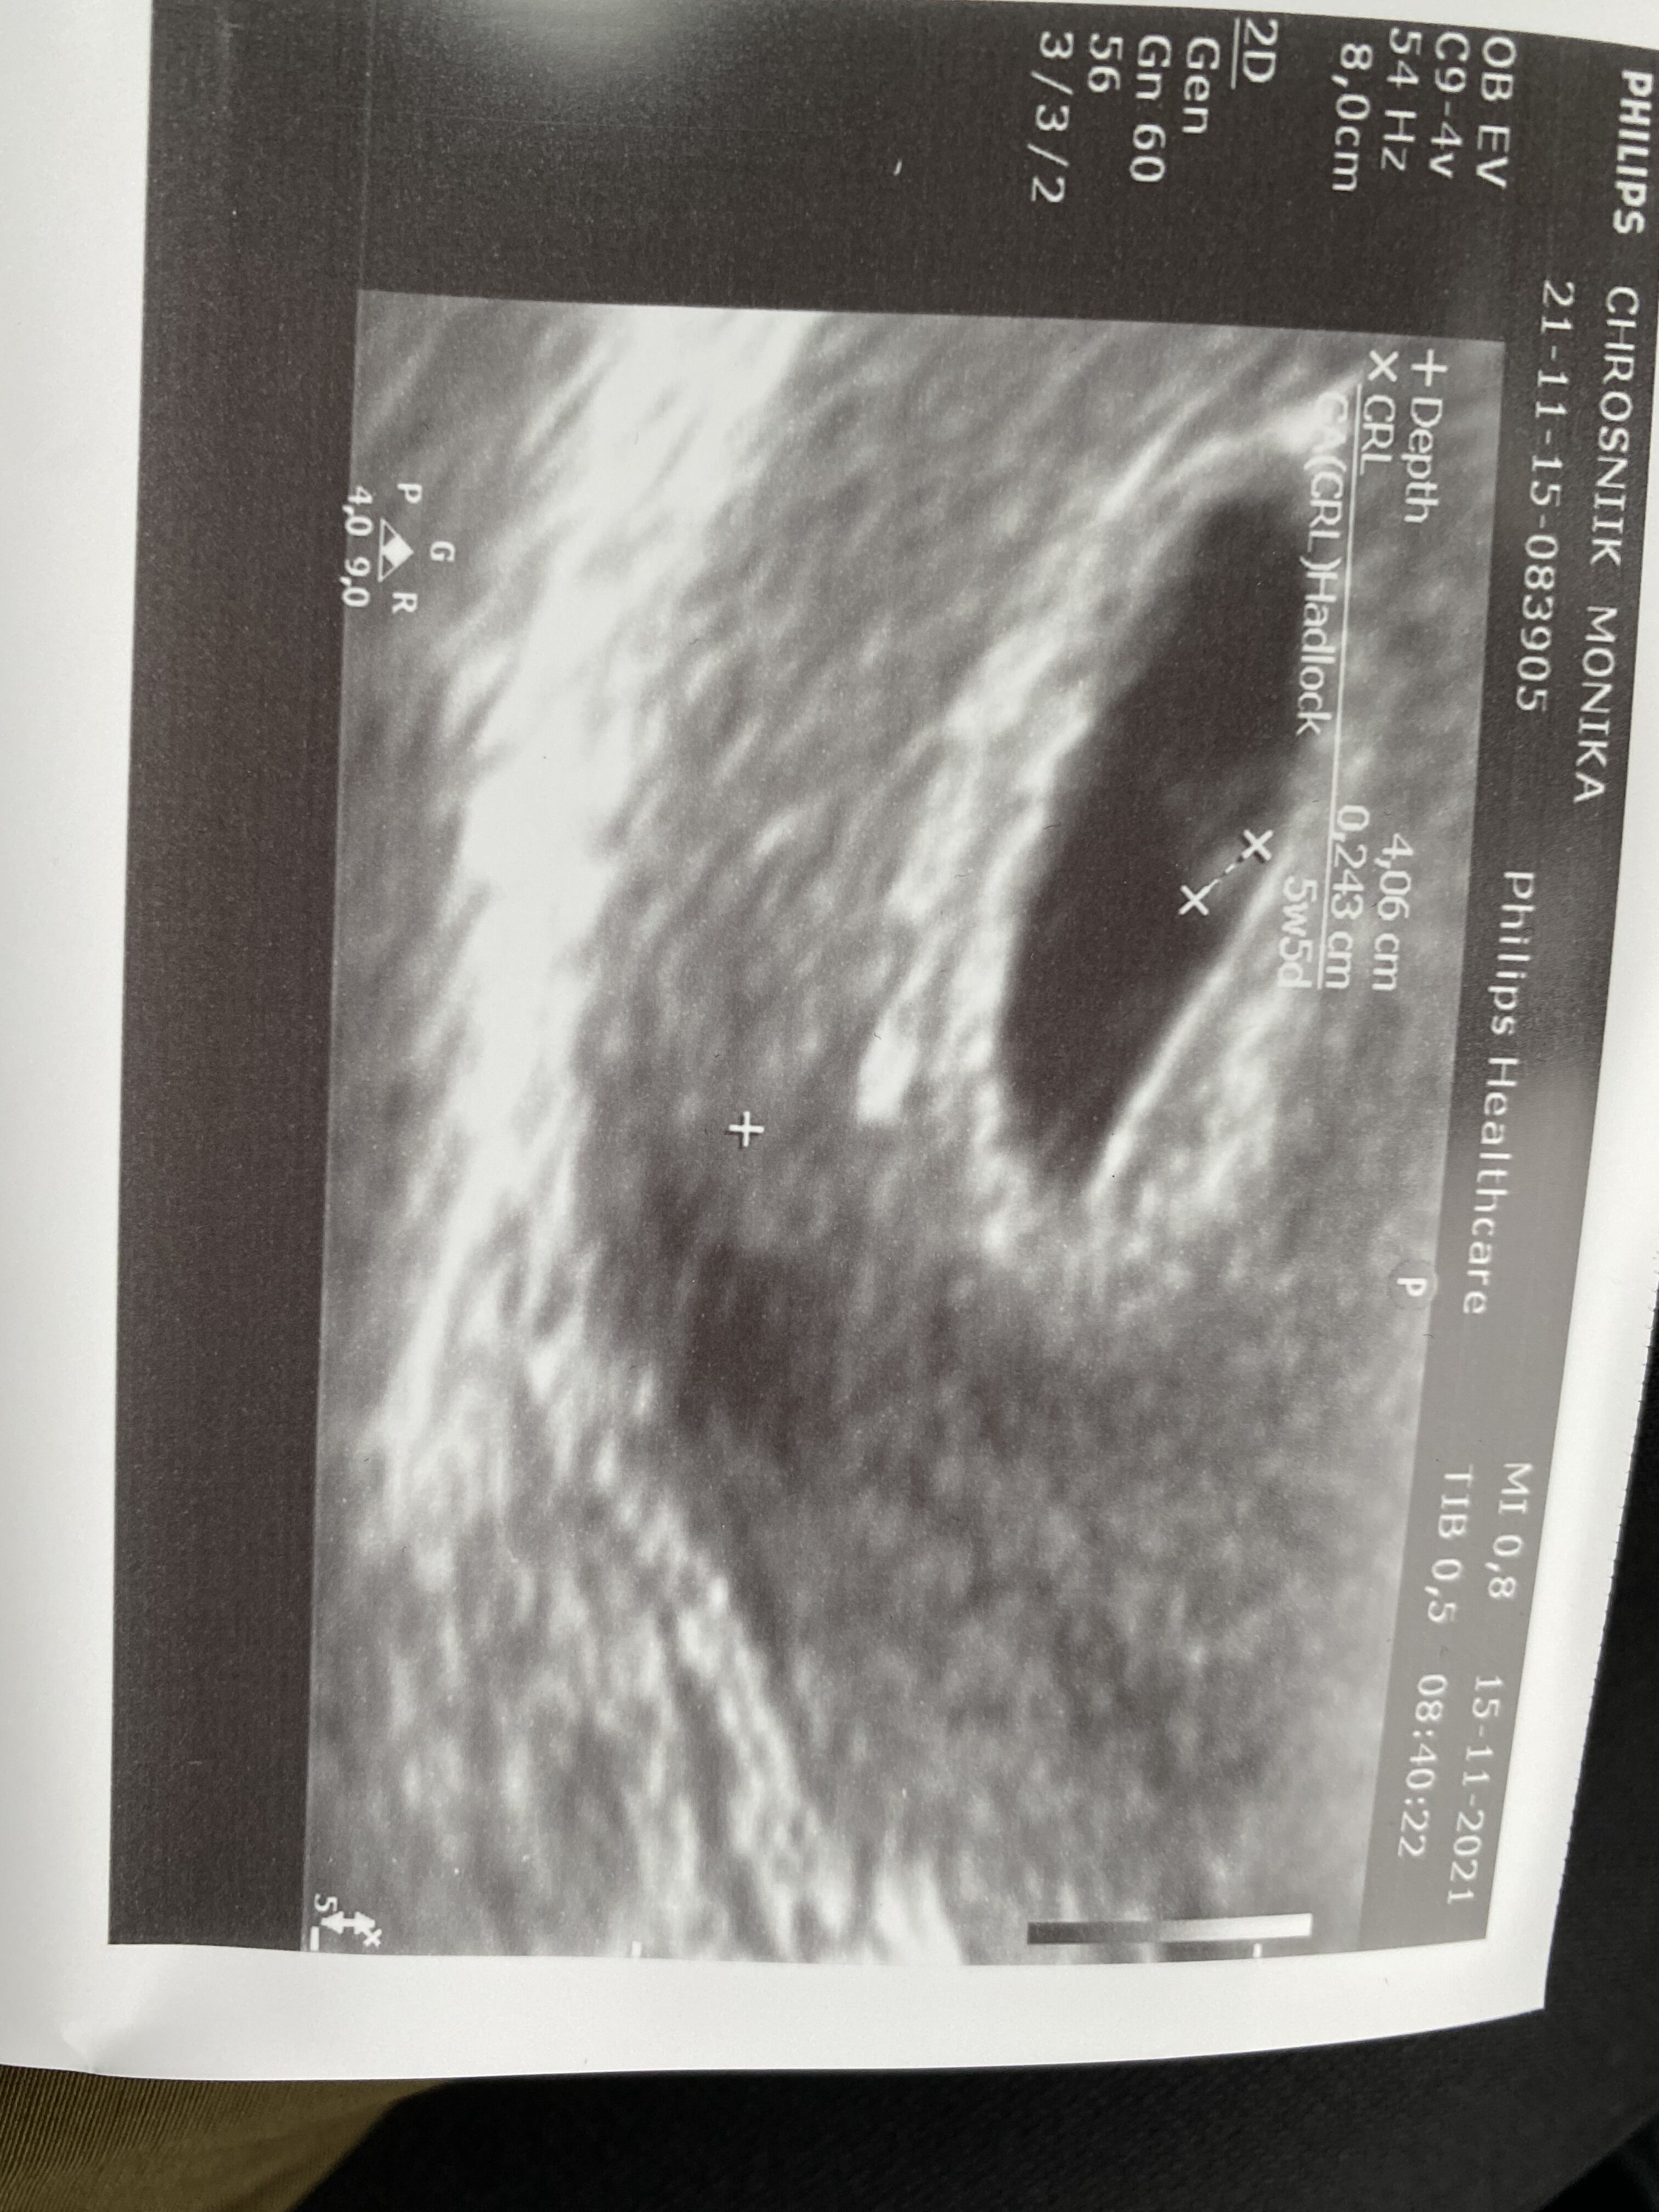

Hej, hej i ja do was dołączam u mnie 6 tydzień i 5 dni ale na usg wychodzi ciąża o tydzień młodsza, dołączyłam dopiero do was bo myślałam ze moja ciąża nie rozwinie się, miałam straszne plamienia, ale na szczęście ciąża rozwija sie [emoji4][emoji3059]Zobacz załącznik 1337018

• 2B203BBD-B2B5-4F1B-8CA7-70670880E3C8.png

2B203BBD-B2B5-4F1B-8CA7-70670880E3C8.png

127,8 KB · Wyświetleń: 58